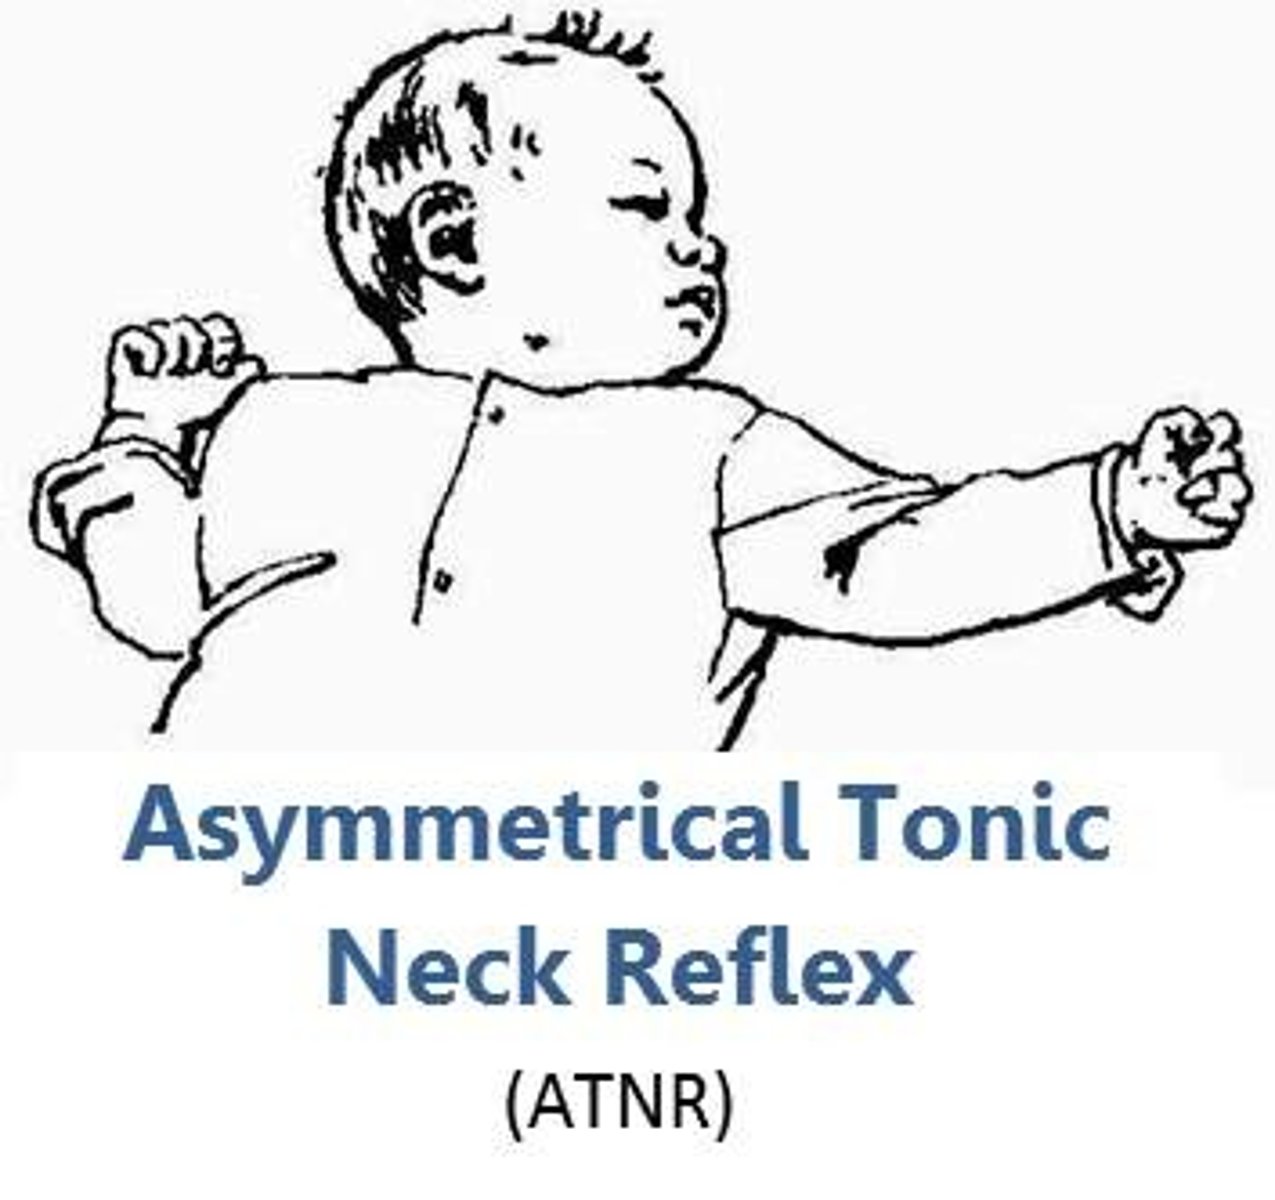

Which reflex: turn infants head and neck to one side to elicit extension of upper & lower extremities on the side to which the head is turned, with flexion of the C/L upper extremity (fencing posture)

ATN (Asymmetric tonic neck)